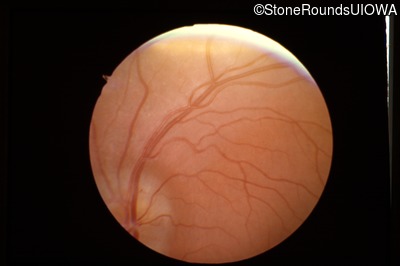

Visit at age: 18 years

Fundus Photography - Right - 20/40 +2

Exemplar